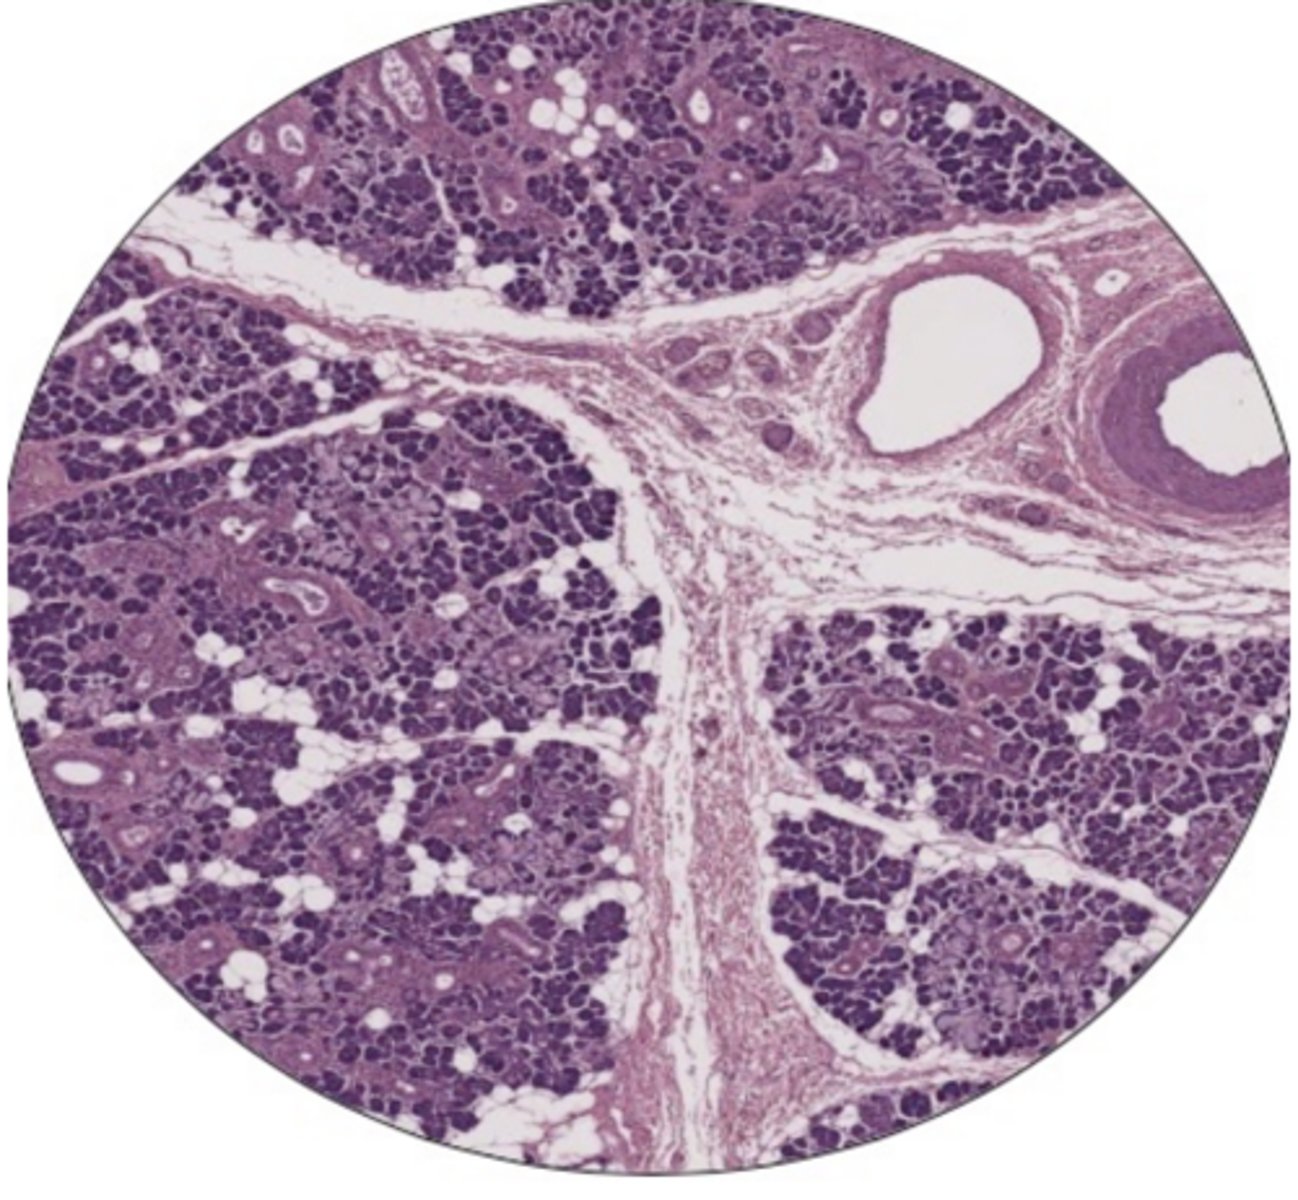

pancreatic acini

Pancreatic Iselts

glomerulus

convoluted tubules

collecting duct

seminiferous tubule

leydig cells